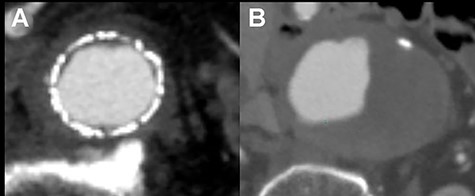

The patient recovered uneventfully, however, 1 year after open conversion, CT revealed a significant increase in the size of the unreplaced infrarenal aorta (Figs 3A, 4A and B). Reoperation was performed to treat the new aneurysm and on intraoperative findings, it was a true aneurysm. Abdominal aortic replacement was performed, however, infection of the vascular prosthesis occurred as a complication of this second open surgery. The infection was not controlled, and unfortunately, the patient died.

One year after open conversion, CT scan showing the significantly dilated infrarenal aorta (A) compared with the aorta before open repair (B).